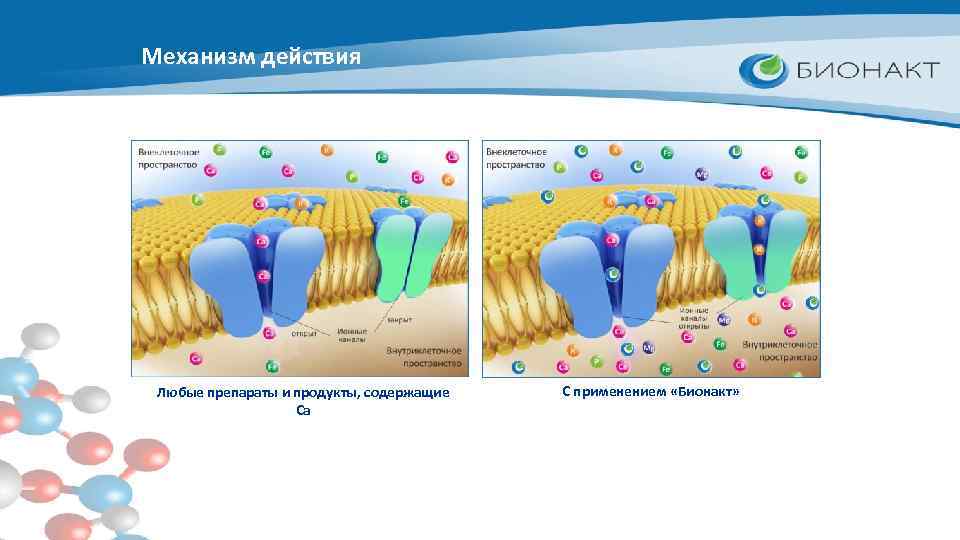

Механизм действия Любые препараты и продукты, содержащие Са С применением «Бионакт»